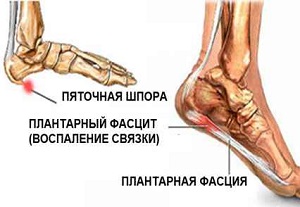

Процесс развития болезни

Фасции представляют собой соединительные ткани опорно-двигательного аппарата, которые выполняют роль естественного поддерживающего каркаса для мышц и связок. Подошвенная фасция является наиболее нагруженной частью в организме человека.

При ходьбе, беге и в положении стоя стопа часто подвергается значительным нагрузкам, что может приводить к микроповреждениям и разрывам фасций. Именно это и становится причиной появления пяточной шпоры.

При постоянных микротравмах фасция не успевает восстановиться, что приводит к воспалению тканей и возникновению болевых ощущений. Процесс заживления сопровождается образованием рубцовой ткани и костных наростов.

Название патологии выбрано не случайно — на рентгеновских снимках видно костное образование на пятке, напоминающее шпору.

Наиболее часто данное заболевание развивается на фоне плоскостопия и артроза голеностопного сустава, поскольку неправильное распределение нагрузки на голеностоп влияет на развитие фасциита. Другие причины возникновения этого заболевания будут рассмотрены далее.